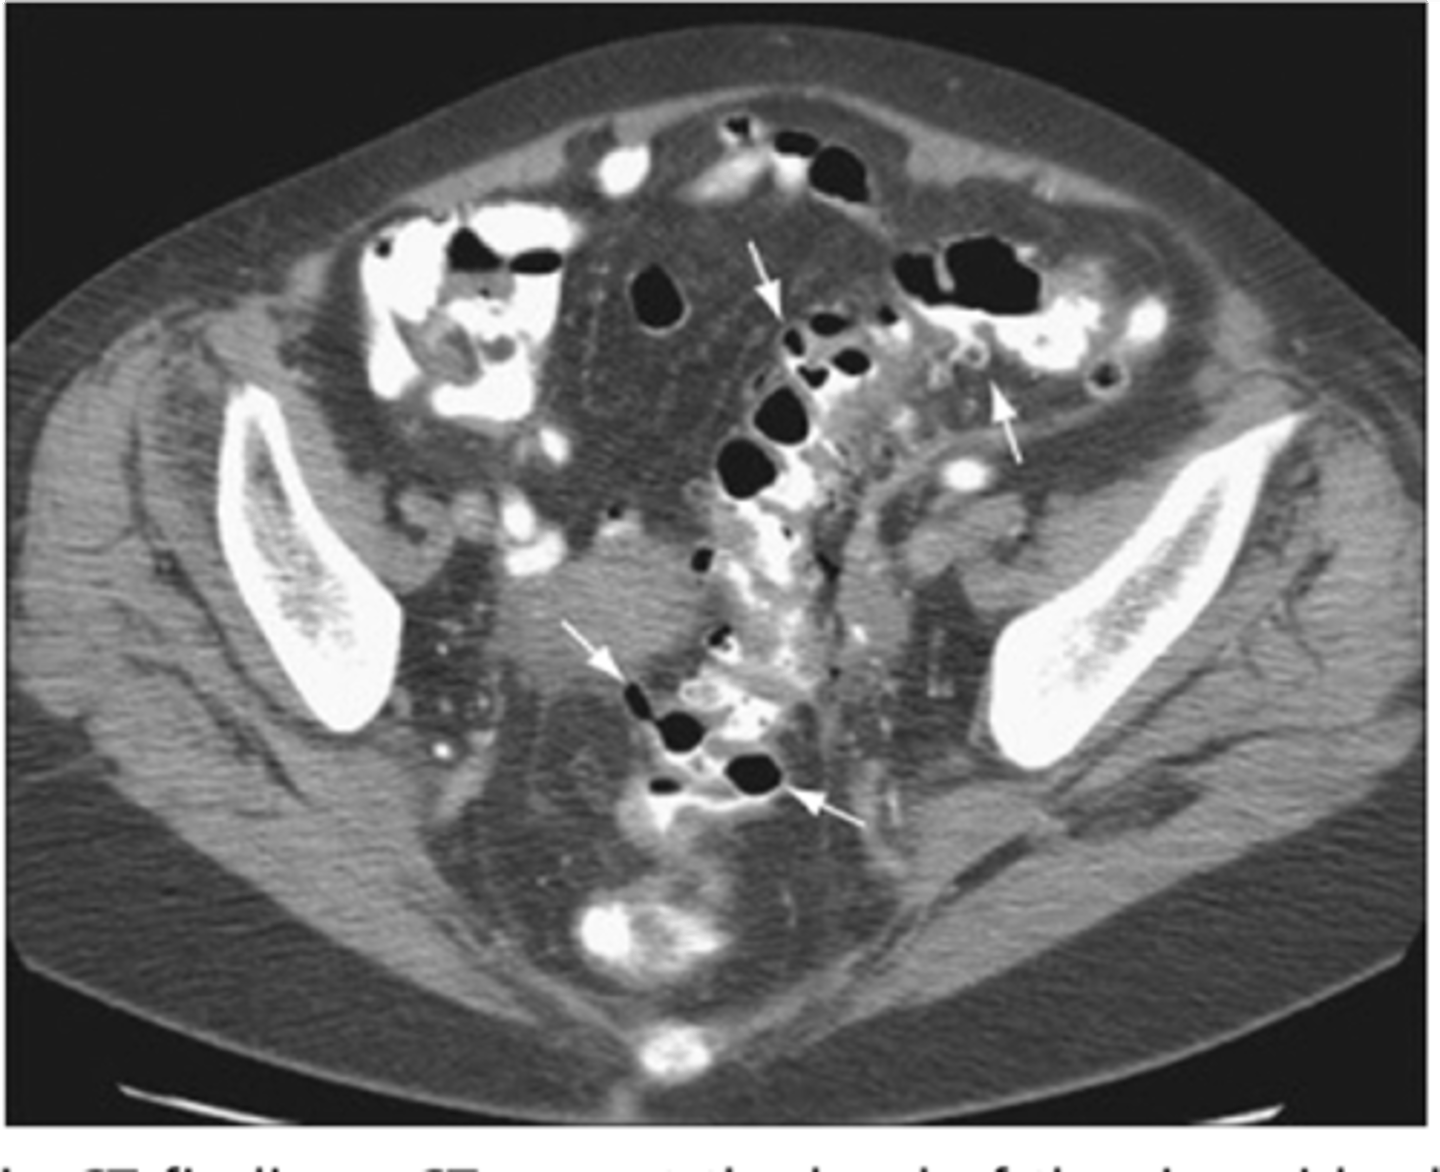

diverticulitis

macroscopic inflammation of a diverticulum, may lead to microperforation, abscess, or peritonitis

S/Sx: aching LLQ pain, N/V, constipation or loose stools

Abdominal CT + f/u Colonoscopy or CT colonography